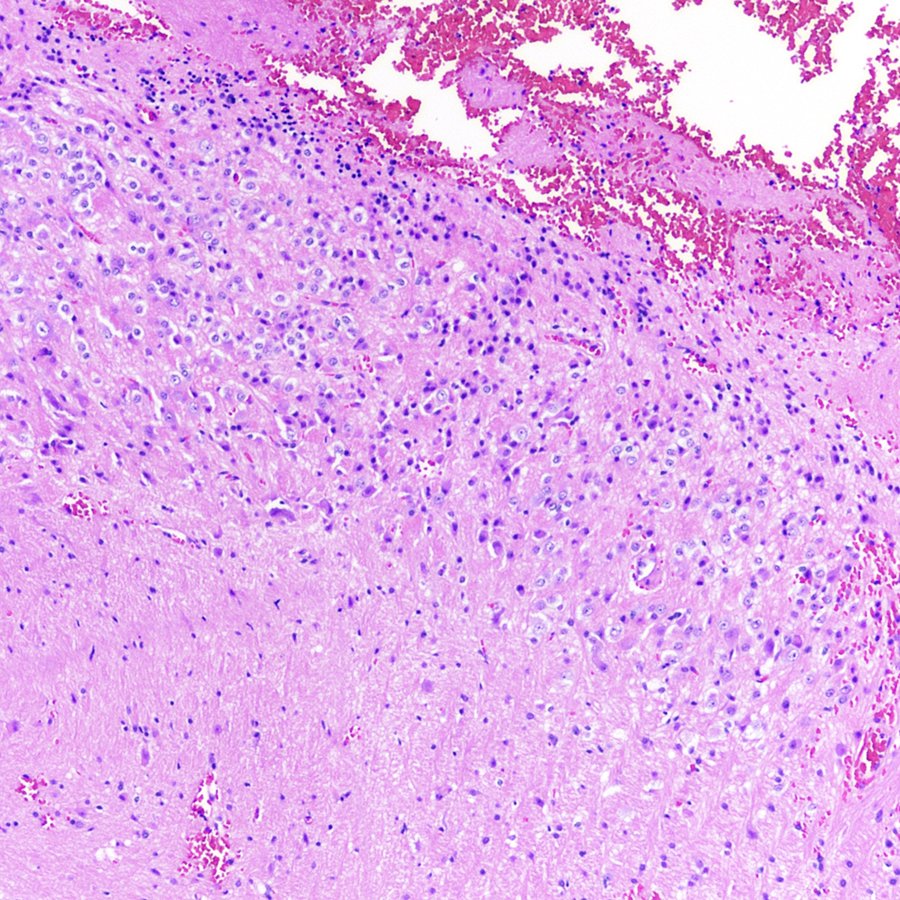

Our recently published manuscript in Cancer Cell – Diffuse hemispheric glioma, H3G34R/V-mutant (H3G34-DHG) - cell.com/cancer-cell/fu…